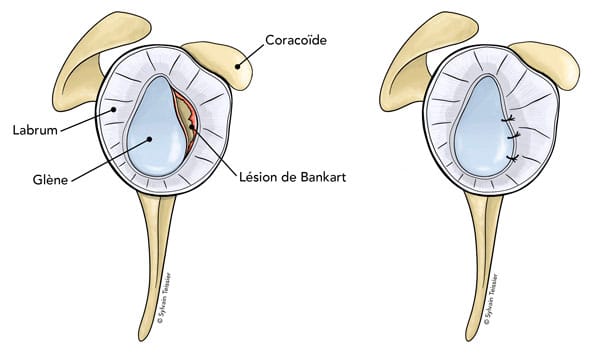

L’instabilité de l’épaule peut se manifester de plusieurs façons : luxations récidivantes, sensation d’instabilité et/ou douleurs.

Ne sera abordée dans cet article que l’instabilité antérieure, post traumatique, la plus fréquente.

Elle résulte en général d’un premier évènement traumatique : la luxation d’épaule .

L’arthroscanner et l’IRM permettent de confirmer le diagnostic et de mieux cerner les causes de cette instabilité

Il existe plusieurs interventions chirurgicales pouvant stabiliser l’épaule.

- La stabilisation capsulaire +/- associée à un remplissage de l’encoche